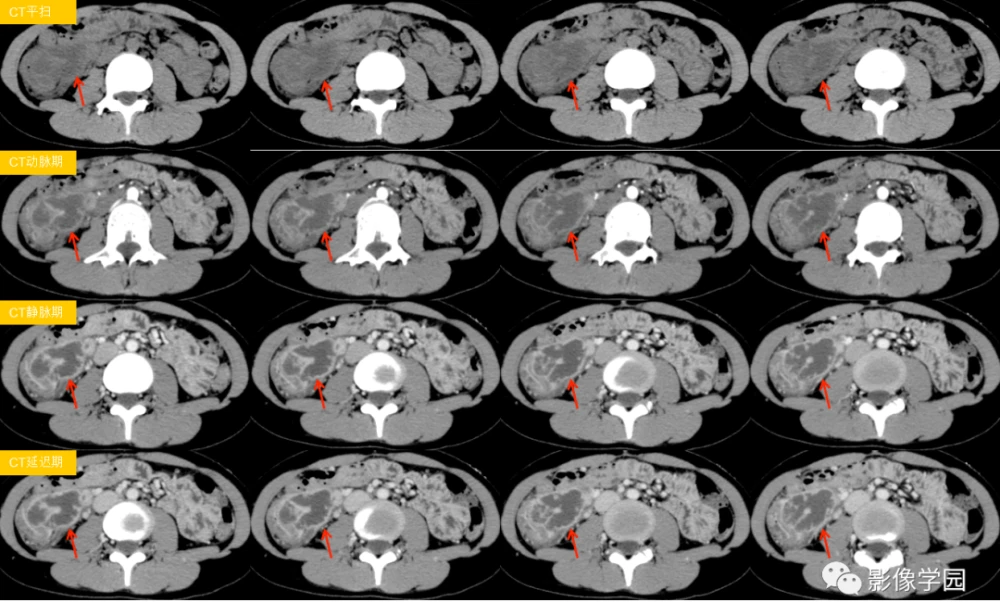

但是,医生们可不是随便下结论的。他们得仔细看看,你是不是真的得了克罗恩病。首先,他们会问你一大堆问题,比如肚子疼多久了,有没有拉肚子,体重有没有下降之类的。然后,他们会让你做一些检查,比如验血、做肠镜,甚至有时候还要做CT或者MRI,看看肠子里到底发生了什么。

关键是,克罗恩病和其他一些病很像,比如溃疡性结肠炎,或者是一些感染性的肠病。所以,医生们得非常小心,不能搞错了。